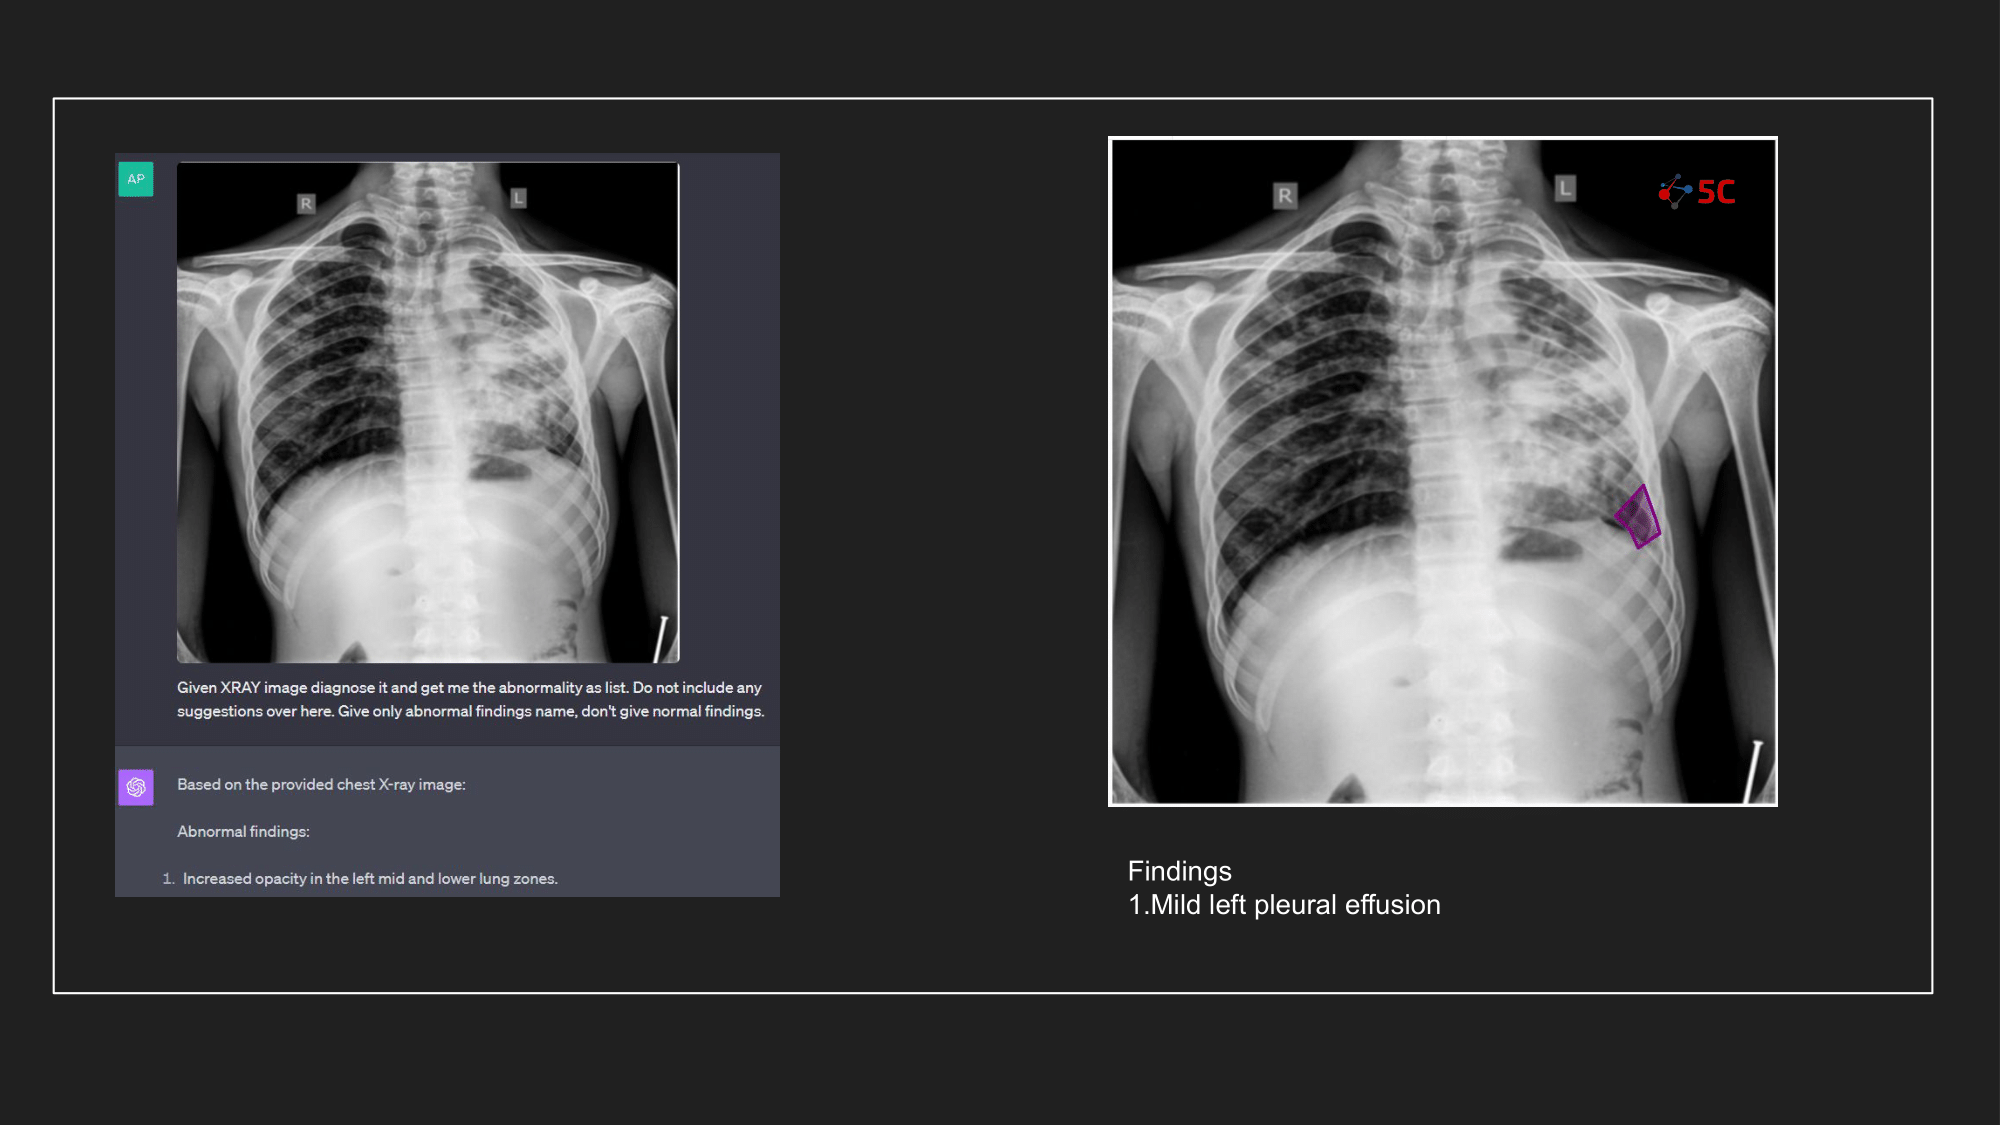

To gauge GPT-4V's prowess in detecting pleural effusion, an experiment was conducted with 10 random chest X-rays known to have pleural effusion. The XRays were sent to GPT-4V, Radiologists as well as to 5C's AI.

Presented below are the results from the experiment.

The output from GPT-4V and from 5C's AI model for the Chest XRays are provided at the end of the post.